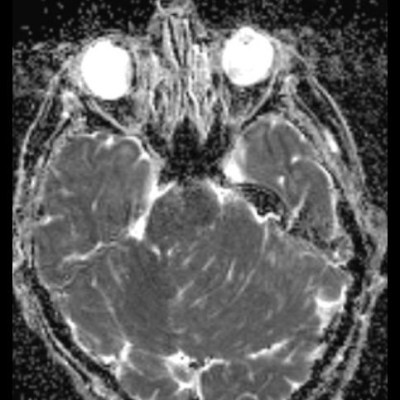

24 yaş, E

Baş ağrısı

Lhermitte duclos

Lhermitte-Duclos hastalığı (Dysplastic cerebellar gangliocytoma)

Dysplastic cerebellar gangliocytoma(Lhermitte-Duclos hastalığı)

Lhermitte-Duclos hastalığı

Displastik serebellar gangliositoma